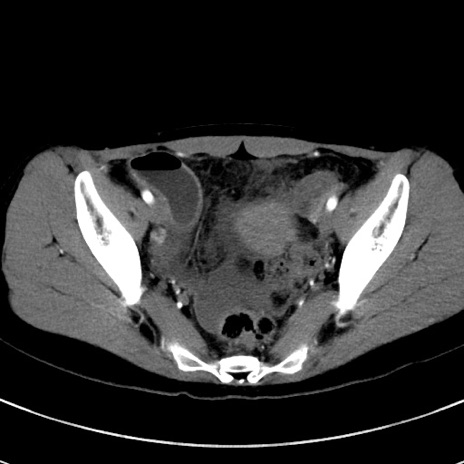

冠状断像

【症例】20歳代女性

【主訴】嘔吐、下腹部痛

【現病歴】昨日夕食後に嘔吐し下腹部痛が出現。本日になっても嘔吐持続し改善しないため来院。

【身体所見】意識清明、BT 37.2℃、BP 108/67mmHg、腹部:平坦、やや硬、下腹部正中から右にかけて圧痛あり、反跳痛軽度あり、tapping pain(+)。

【データ】WBC 13600、CRP 14.94